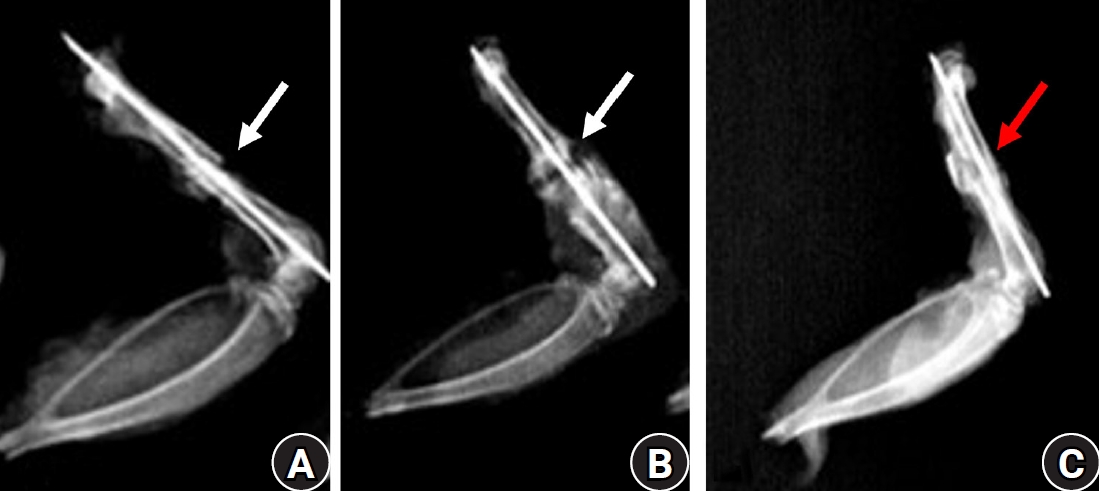

Fig. 1.

Lateral radiographs of rat femora at 7 weeks after fracture. (A) The diclofenac group and (B) the celecoxib group show persistent radiolucent fracture lines (white arrows), defined as linear lucencies at the original fracture site indicating incomplete cortical bridging. (C) The control group demonstrates a consolidated bridging callus (red arrow) without residual fracture lucency.

Radiographic findings

The radiographs of nearly 90% of the animals treated with diclofenac and 65% of those treated with celecoxib by the end of 7th week postoperative still showed the gap between the two edges of the healing bones and were marked as persistent radiolucent fracture lines by two observers. In contrast, all animals in the control group exhibited well-formed bony callus (Fig. 1).